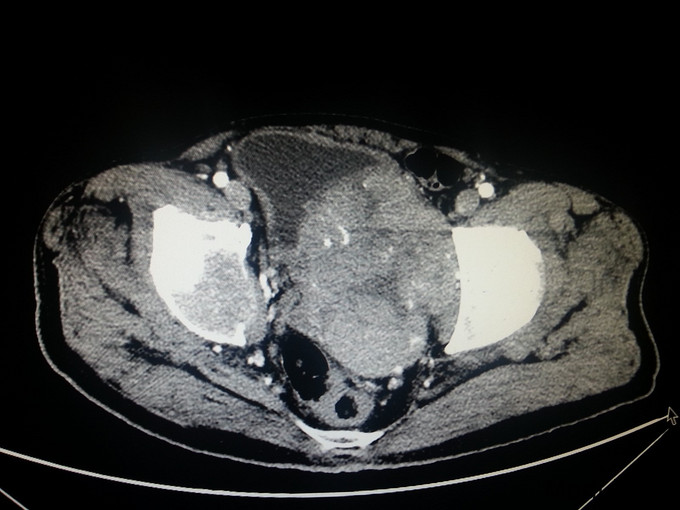

患者,男,68岁,因门诊CT检查发现前列腺肿瘤、骨转移入院

前列腺穿刺病理 :前列腺癌 Gleason4+4 PSA>100ng/ml fPSA>30ng/ml

患者入院后经会阴前列腺穿刺活检,病理诊断为前列腺癌 Gleason4+4 ;予以口服氟他胺以及静脉注射唑来膦酸、戈舍瑞林缓释剂皮下注射治疗; 治疗半年后复查 CT提示前列腺肿瘤缩小;PSA45ng/ml;患者一般情况明显好转